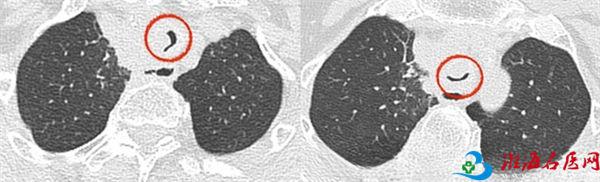

近日,饱受憋喘症状所折磨的杜女士来到徐州一院呼吸与危重症医学科就诊。三病区主任崔文洁了解发现杜女士既往有甲状腺恶性肿瘤病史,现出现多部位脏器及淋巴结转移,近期胸部CT可见气管旁占位及气管内肿物,是导致反复出现胸闷、憋喘不适的原因。由于杜女士气道内肿物大,有较大的出血及窒息等风险,且距离声门较近(仅4厘米),手术操作难度大,辗转多家医院均因难度大、风险高而未实施气管镜下腔内介入治疗。她即刻为患者安排绿色通道,完善相关检验、检查,评估病情,为支气管镜检查做术前准备。

7月23日,主任医师施海和副主任医师陈云峰、袁杰清相互配合,经细致术前准备,对患者实施全麻支气管镜下腔内病变高频电刀、氩离子凝固、冷冻联合治疗。全麻经喉罩进镜后,声门下4厘米处见管腔内新生物,导致管腔重度狭窄,直径6毫米左右的气管镜勉强可挤过气道。

专家们运用电刀与氩气刀切除气道内占位,切除后的创面冻融处理,避免增生。手术过程约40分钟,术中患者生命体征平稳,活检部位仅少量出血。术后患者胸闷、憋喘症状得到明显改善。